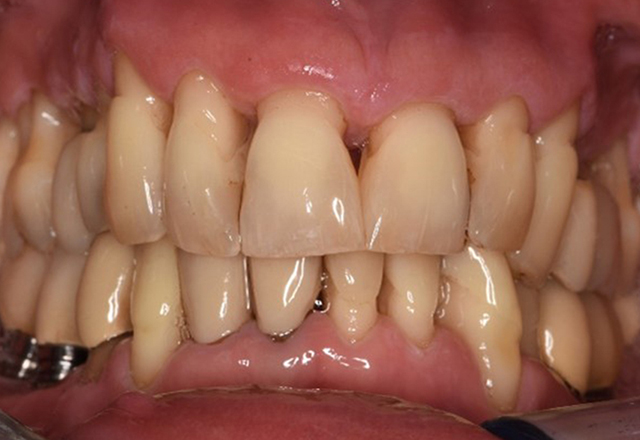

The transplant patient with gingival overgrowths

A 71-year old patient presents with having previously undergone a kidney transplant and with a history of hypertonia (high blood pressure). Due to his medical history, long-term medication with cyclosporine is required to suppress the immune system, as well as amlodipine to lower blood pressure. The patient also reports sensitive and bleeding gums. From an oral health perspective, the patient has undergone dental restoration and has eight missing teeth, pronounced gingival growth, and grade B, stage II periodontitis with active pockets and initial root caries on tooth 22. The caries risk assessment determines a moderate risk of caries (API 60). The following treatment recommendations can be determined for the prophylaxis session. more